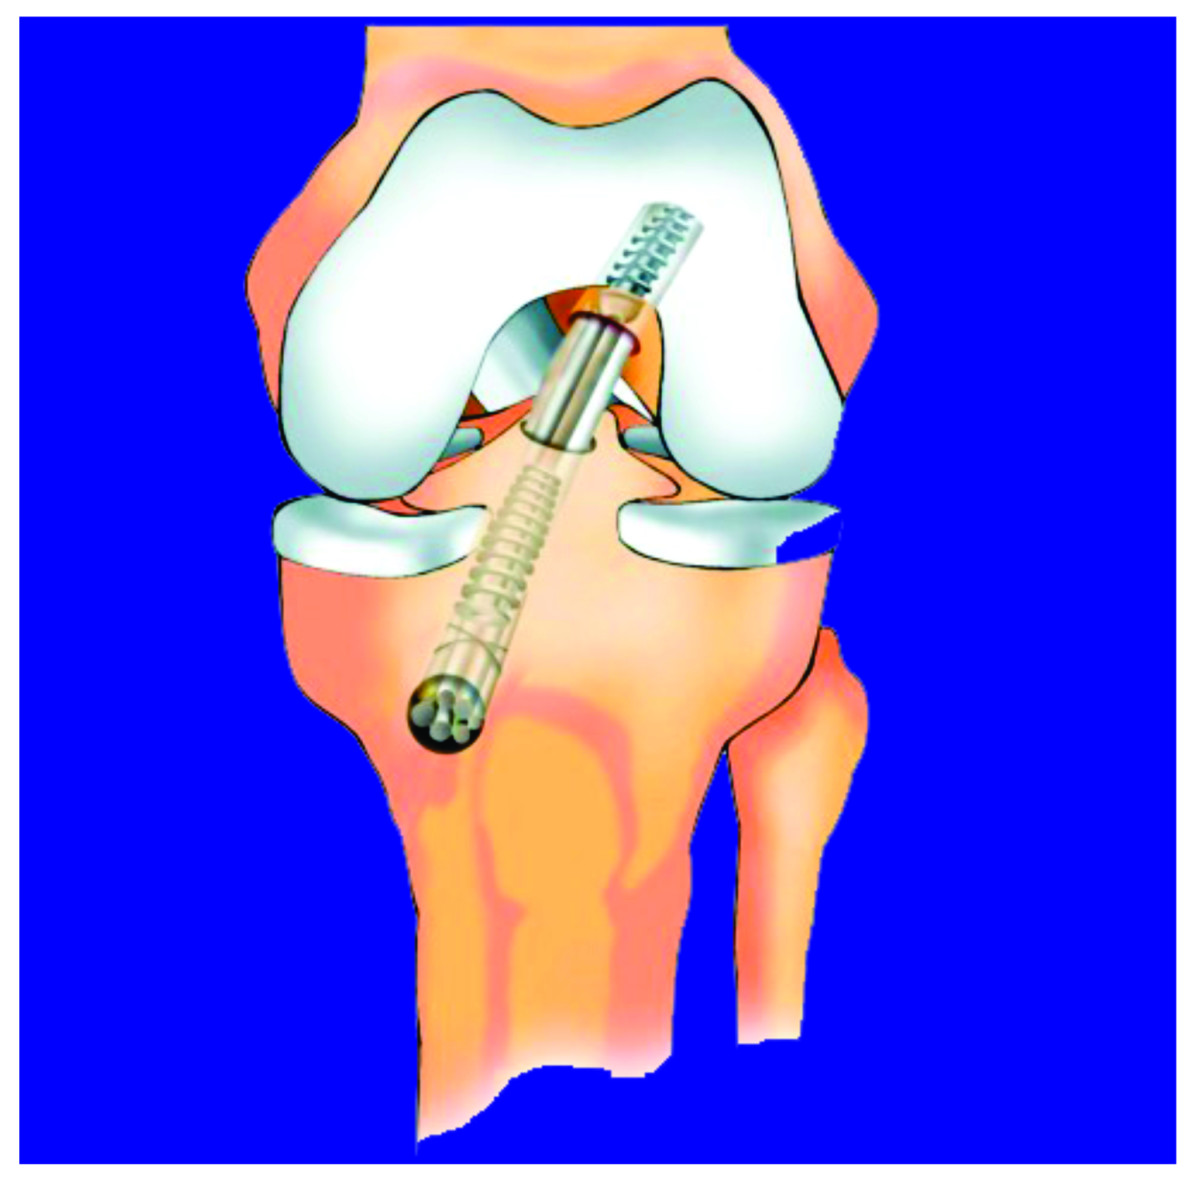

São indicados para utilização em qualquer situação de fixação de estruturas não ficando somente ligados a fixação de ligamentos cruzados do joelho. Assim sendo possível sua utilização diversificada.